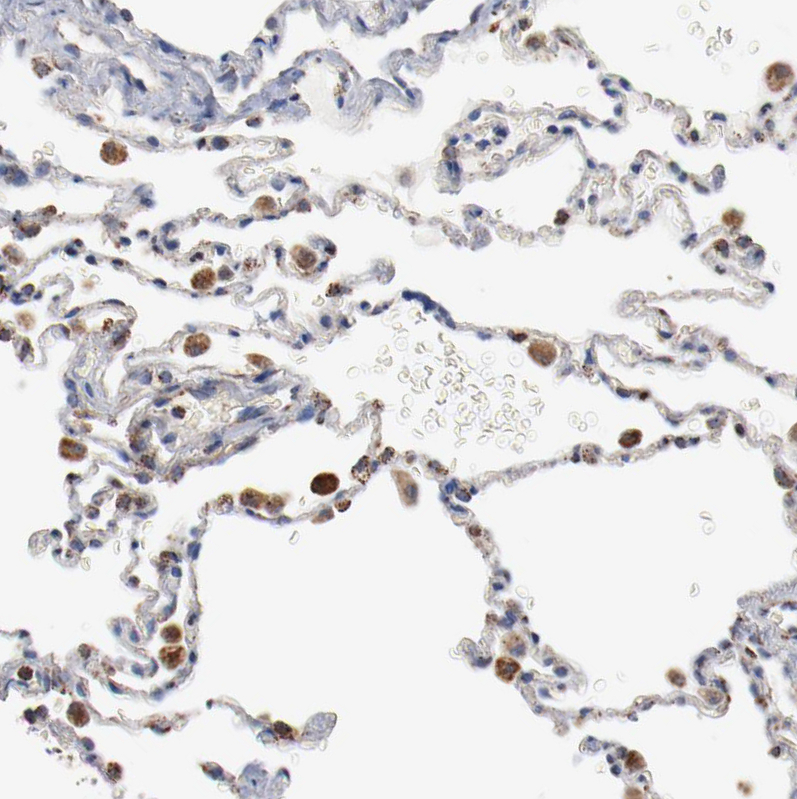

Immunohistochemical staining of human kidney shows strong positivity in cytoplasm granular in cells in tubules.